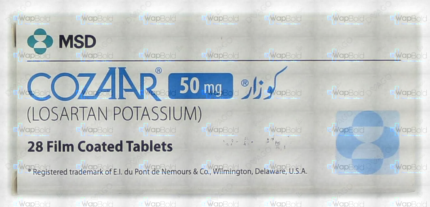

Cozaar Tablets 50Mg (1 Box = 2 Strips) (1 Strip = 14 Tablets)

₹596.40 Original price was: ₹596.40.₹566.60Current price is: ₹566.60.